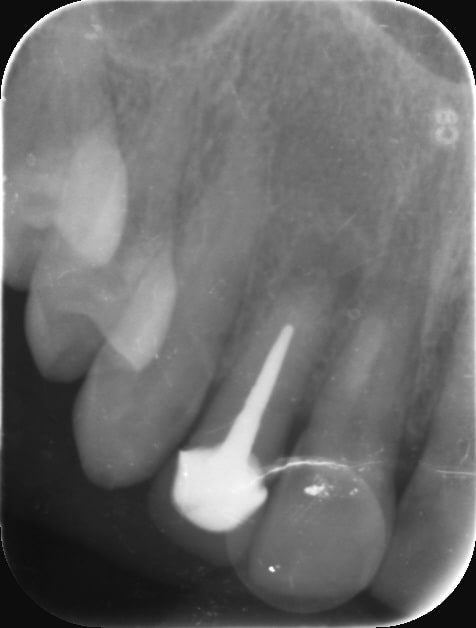

Qu'est ce que vous faites dans le cas de gros tenons comme là bande de vieilles branches ? 22 et 12 sur la même patiente

Img 0702 yvtk5b - Eugenol

Img 0703 xwhbb3 - Eugenol